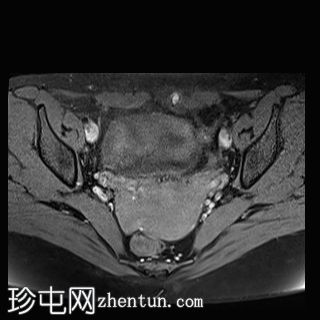

轴位

T2血流加权像

MRI特征符合剖宫产术后瘢痕子宫内膜异位症,表现为特征性T1高信号伴T1FS持续存在,T2低信号伴内部高信号灶,病灶边缘浸润于腹前壁肌肉内,以及对比增强。

影像学表现符合病灶内出血成分,提示既往剖宫产瘢痕处存在异位子宫内膜组织。

在磁共振成像(MRI)上,瘢痕子宫内膜异位囊肿通常表现出与盆腔子宫内膜异位病灶相似的影像学特征。值得注意的是,它们在脂肪抑制T1加权像上表现为高信号强度区域,对应于异位子宫内膜腺体和出血。